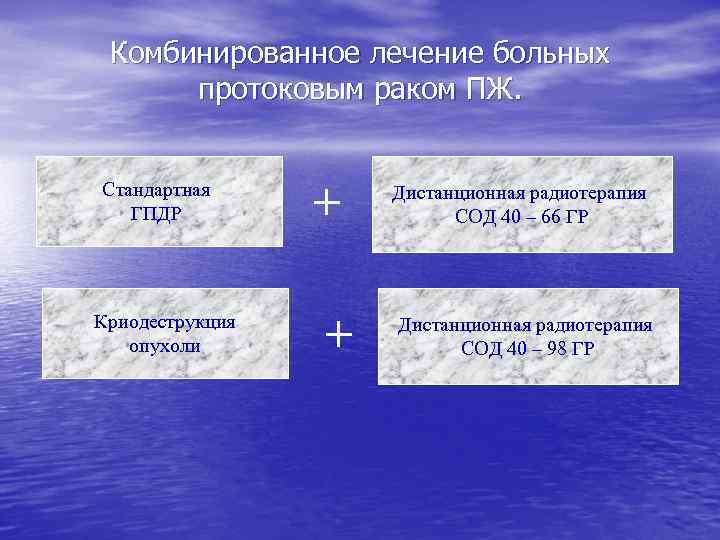

Комбинированное лечение больных протоковым раком ПЖ Стандартная ГПДР Масляная х/эмбол. ГДА + ДСРПЖ Криодеструкция опухоли + Дистанционная радиотерапия СОД > 40 ГР Стандартная ГПДР + + + Дистанционная радиотерапия СОД > 40 ГР

Комбинированное лечение больных протоковым раком ПЖ. Стандартная ГПДР Криодеструкция опухоли + + Дистанционная радиотерапия СОД 40 – 66 ГР Дистанционная радиотерапия СОД 40 – 98 ГР